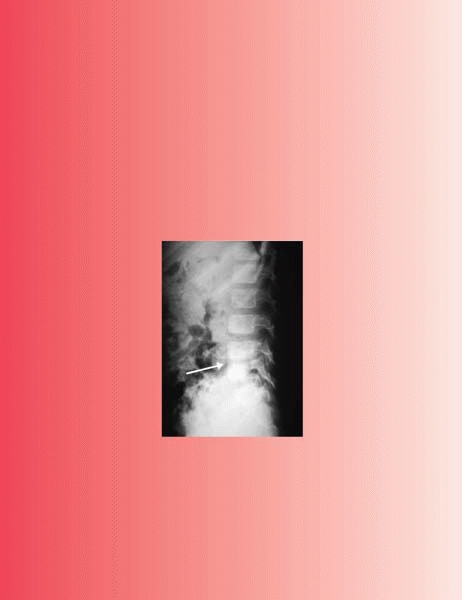

toddler’s fracture does not have to be in the tibia; it can be in the

calcaneus or elsewhere (Fig. 11-1).

▪ FIGURE 11-1

A “toddler’s fracture” does not always have to be in the tibia. Children who jump down stairs or off playground equipment may sustain a fracture of the calcaneus that can be very difficult to see on initial radiographs. This calcaneus “toddler’s fracture” (arrow) revealed itself after 6 weeks in a short leg cast. |